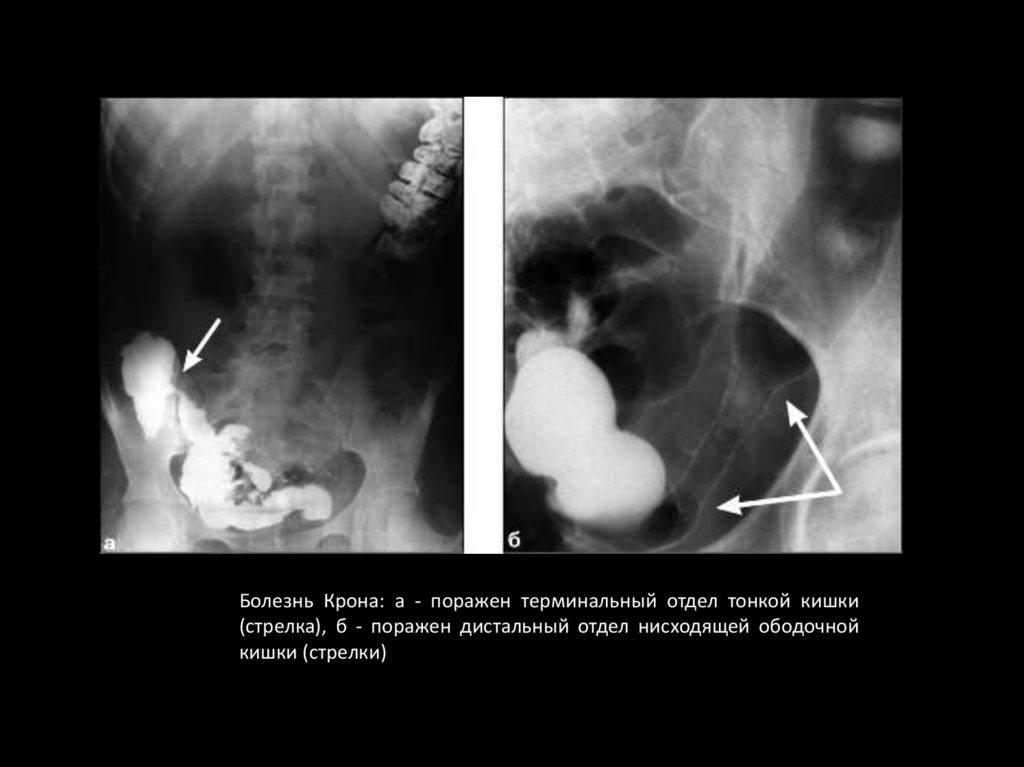

Болезнь Крона: а - поражен терминальный отдел тонкой кишки

(стрелка), б - поражен дистальный отдел нисходящей ободочной

кишки (стрелки)

111. РЕГИОНАЛЬНЫЙ ЭНТЕРИТ И ГРАНУЛЕМАТОЗНЫЙ КОЛИТ (БОЛЕЗНЬ КРОНА)

Первая стадия

•Утолщение, выпрямление и даже исчезновение складок слизистой

оболочки.

•Контуры кишки становятся неровными, зубчатыми.

•Затем вместо привычной картины складок обнаруживаются

множественные

округлые

просветления,

обусловленные

островками воспаленной слизистой оболочки. Среди них могут

выделяться полосковидные тени бария, отложившегося в

поперечных трещинах.

•В области поражения кишечные петли выпрямлены, сужены.

112. РЕГИОНАЛЬНЫЙ ЭНТЕРИТ И ГРАНУЛЕМАТОЗНЫЙ КОЛИТ (БОЛЕЗНЬ КРОНА)

Вторая стадия

•Значительное сужение кишечных петель с образованием

Рубцовых перетяжек длиной от 1—2 до 20—25 см.

•Стенозированный участок может выглядеть на снимках как

узкий неровный канал (симптом “шнура”).

•В отличие от синдрома нарушенного всасывания нет

диффузного расширения кишечных петель, гиперсекреции и

фрагментации контрастного вещества и ясно выражен

гранулярный характер рельефа внутренней поверхности кишок.